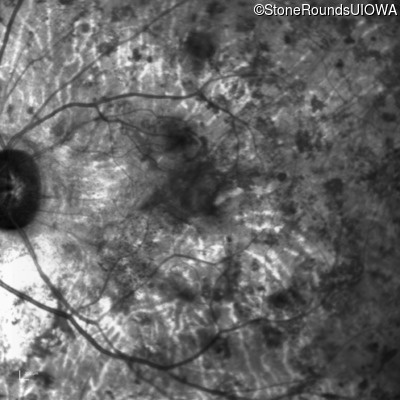

Type 1 Usher Syndrome (IB1a)

This 62 year old man has had profound hearing loss since birth and has communicated using sign language for his entire life. He first noticed a problem with his vision at about age 11 when he noticed night blindness and began to trip over objects that he should have seen.

Type 1 Usher Syndrome USH1C Thr78 ins1aC Thr78 ins1aC AR